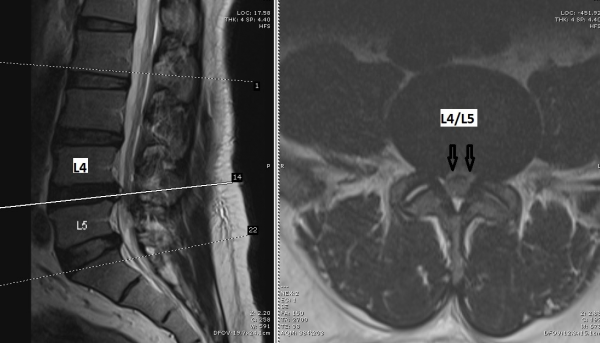

安蒲很肯定自己的膝盖不曾受伤,所以第二个原因也可以排除。接下来,我给他做了磁力共振扫描,结果发现他的腰椎第4和第5节椎间盘胶质凸出,压迫双脚的神经线,导致出现马尾症候群(Cauda Equina Syndrome)的症状。